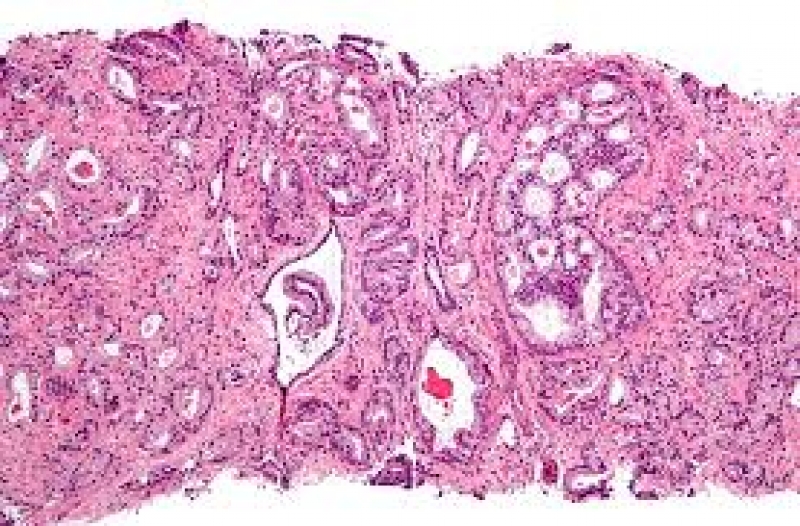

Potrivit Institutului Naţional de Cancer, boala este a cincea cauză de deces din Statele Unite. Se estimează că în 2019 au murit 22,840 de persoane din cauza leucemiei. Leucemia acută mieloidă (AML) se clasează pe locul doi ca fiind cea mai comună formă a acestei boli. Afecţiunea se răspândeşte rapid, iar rata de supravieţuire este foarte mică.

Mai puţin de o treime dintre persoanele care suferă de leucemie acută mieloidă trăiesc cinci ani după ce au fost diagnosticate. Celulele canceroase în cazul leucemiei acute mieloidă se divizează mai rapid decât ar putea tratamentul să acţioneze. Găsirea unei noi terapii prin care să se trateze aceste celule canceroase este crucială pentru prelungirea duratei de viaţă a pacienţilor care suferă de leucemie acută mieloidă, scrie portalul csid.ro.

Celulele canceroase folosesc schimbările din metabolism, atunci când apare ca rezultat o reacţie chimică, celulele se schimbă, cresc sau se înmulţesc rapid.